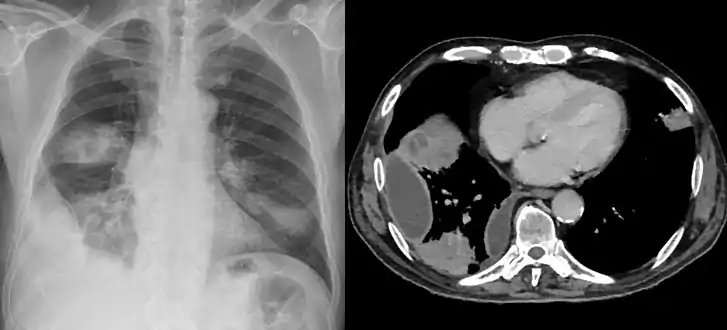

Lungs

Empyema